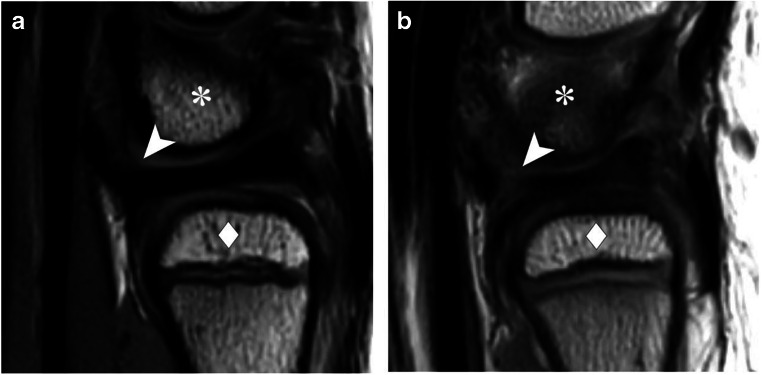

In the sagittal plane, the dorsal and volar RUL were scored as continuous and indiscernible structures with the TFC in 74 (80%) and 55 (60%) observations, respectively, while the volar RUL signal intensity appeared to be discontinuous with the TFC in 23 (25%) observations (Fig. 3). The inter-observer agreement was fair (ICC = 0.23, 95% CI = 0.11–0.36) for volar RUL and poor (ICC = 0.20, 95% CI = 0.07–0.32) for dorsal RUL sagittal morphology. Axial RUL fiber continuity was scored as continuous in 77 (84%) observations of the dorsal RUL and 82 (89%) of the volar RUL. In 5 (5%) observations, the dorsal RUL showed fiber discontinuation, for the volar RUL fiber discontinuation was seen in 1 (1%) observation. For this item, inter-observer agreement regarding the dorsal and volar RUL was poor (ICC = 0.06, 95% CI = −0.07–0.19 and ICC = −0.04, 95% CI = −0.19–0.12, respectively).

Fig. 3.

Sagittal proton-density weighted MRI showing the volar RUL as a structure that is a continuous and indiscernible with the TFC (arrowhead) and b discontinuous with the TFC (arrowhead) in between the ulnar head (diamonds) and lunate bone (asterisks)